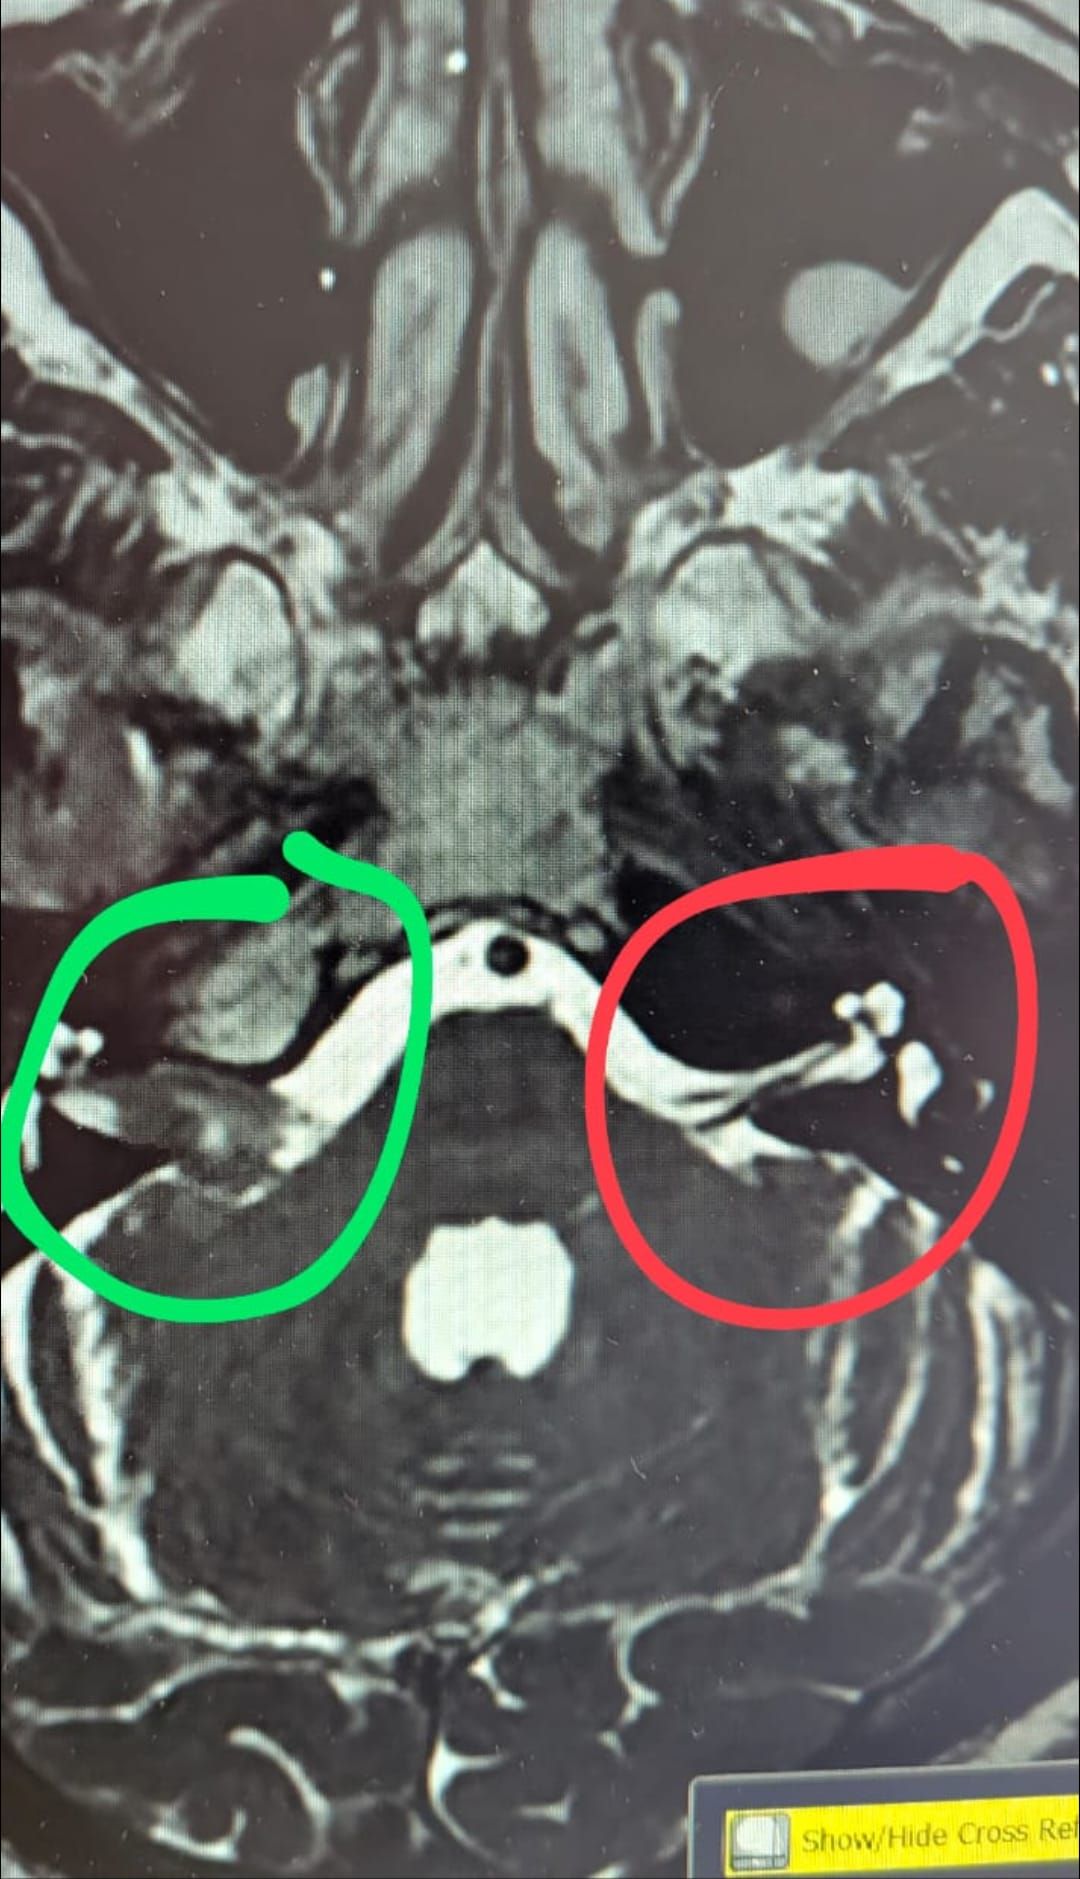

Yeah, sorry edited. It's the 17th! I feel bad for 'missing' an appointment as I know what a burden missed appointments are to the NHS, but I knew nothing about it. Strange how my docs aren't getting copies of stuff too. Anyway, I'm back in the system. This is my head, looking up through my skull from the bottom, eyes would be right at the top of the pic.

Red shows my hearing and balance nerves as they should be (they are the grey lines in the white).

Green shows the nerves are stretched super thin around the tumour - currently 1.8cm.